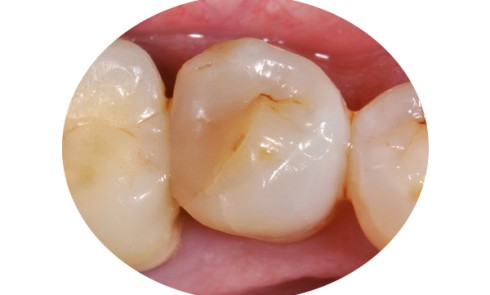

Article réservé à nos abonnés Diagnostic des fractures longitudinales dentaires

Les fractures dentaires longitudinales sont classées en cinq catégories [3] (fig. 1) : – les craquelures de l’émail : il s’agit de fêlures...